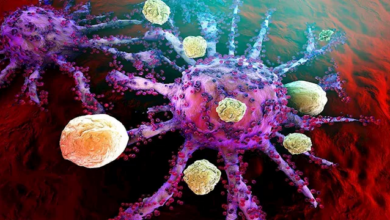

فحص بسيط قد ينقذ المدخنين من الوفاة بسبب سرطان الرئة

تؤكد نتائج دراسة حديثة أن توسيع نطاق فحص التصوير المقطعي المحوسب للصدر قد يساهم في تقليل وفيات سرطان الرئة بشكل كبير، بشرط أن يخضع جميع المؤهلين للفحص وفق معايير محددة.

- تشير النتائج إلى أن توسيع أهلية الفحص قد يساعد في إنقاذ الأرواح، من خلال اكتشاف سرطان الرئة مبكراً وتوفير خيارات علاج أكثر فاعلية.

- أشارت النتائج إلى إمكانية تقليل وفيات سرطان الرئة بشكل ملحوظ إذا شمل الفحص جميع المؤهلين وفق المعايير المحددة.